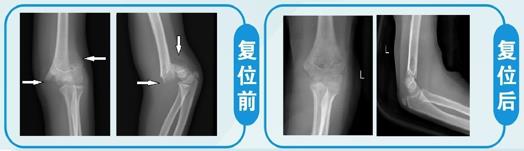

(8)肱骨髁上骨折 常见于儿童,治疗不当可造成肘内翻等后遗症,手术治疗又容易损伤骨骺,影响儿童骨骼生长。手法复位治疗这类骨折具有创作小、对位好、愈合快、功能恢复良好、较少遗留畸形的特色。